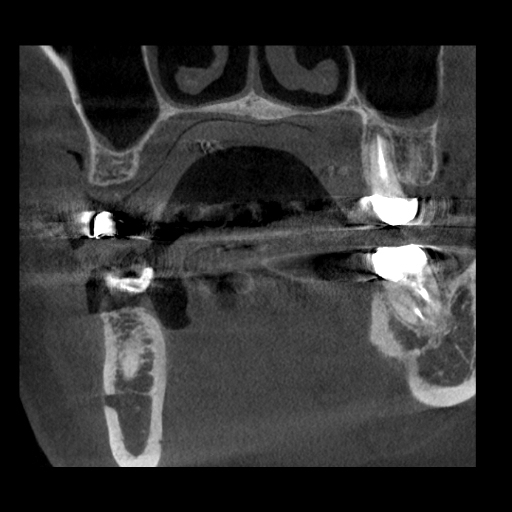

右上インプラント治療に伴うサイナスリフトの症例

Before

After

治療内容

右上の5番を抜歯され、インプラント治療を希望された患者様です。

副鼻腔があり、インプラントを埋入するための骨の量が足りないため、副鼻腔に骨を作る処置(サイナスリフト)を行い、同時にインプラント埋入しました。

理想的な位置にインプラントを埋入することができ、長期予後を獲得することができます。

担当歯科医師:平沼 佳朗

治療期間・回数

約10か月

費用

サイナスリフト込み¥671,000

リスク・副作用

術後に痛みや腫れ、出血を伴います。

口腔内の清掃不良によりインプラントの歯周病(インプラント周囲炎)になる可能性があります。定期的なメインテナンスが必要です。